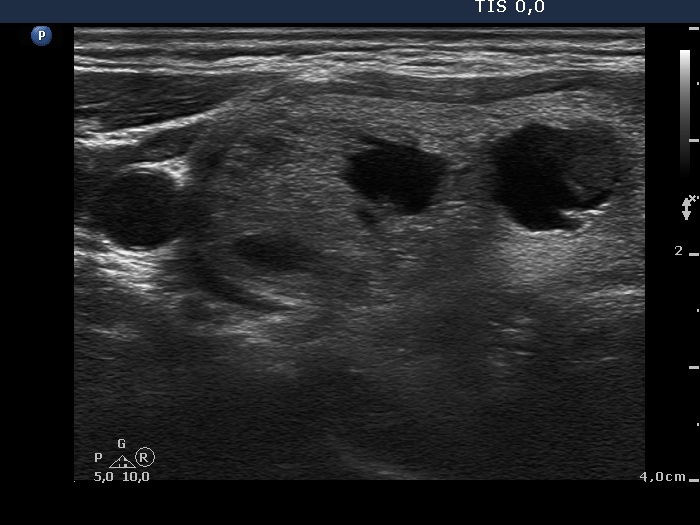

Ultrasonography. Both lobes were composed of multiple nodules of different echogenicities including cystic ones and a large hyperechogenic lesion in the lower part of the right lobe. Except for a moderately hypoechogenic nodule in the dorsal part of the left lobe, the lesions had no oncological significance. The extranodular part was echonormal.